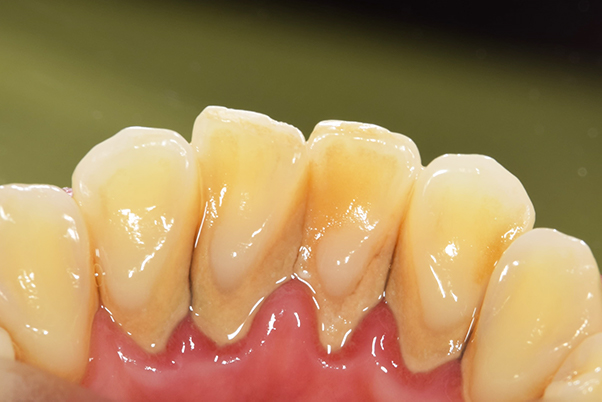

前歯舌側の歯石

【担当医師所見】

歯周病の治療の必要性

ブラッシング方法の教授